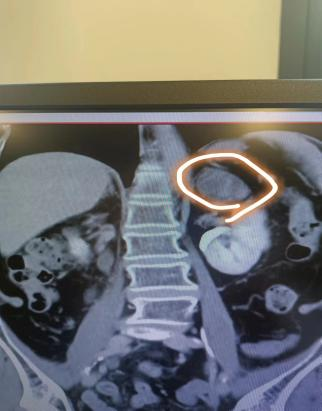

据了解,今年73岁的患者吴女士,因体检发现“左侧肾上腺占位3月”,便到印江县人民医院进一步检查。吴女士患有宫颈癌20多年,一直坚持院外放化疗治疗。经完善相关检查后,术前诊断其为“左侧肾上腺肿瘤”。

患者左肾侧上腺上约3.8cm大小肿瘤